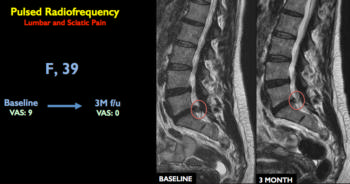

Figure 1. Lumbar spine MRI showing vertebra at baseline and 3 months after treatment

Of the 80 patients treated, 81 percent were pain free one year after a single 10-minute treatment session. Six patients required a second pulsed radiofrequency session. Ninety percent of the patients were able to avoid surgical treatment.

"Following this treatment, inflammation and pain go away. With relaxation of the muscles, the distance between the vertebrae returns," Dr. Napoli explained.